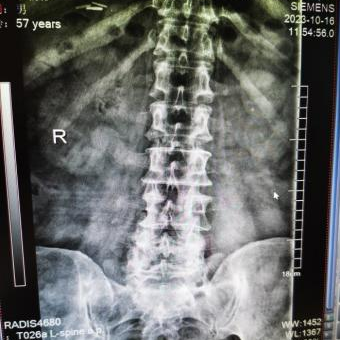

多年来,贵州航天医院各科室紧跟医学前沿,不断强技术、补短板,大力开展新技术、新项目,完成了许多高精尖、高难度、本地区“首例”的技术,填补了医院医疗技术空白,满足了群众日益增长的医疗需求。 贵州航天医院骨科率先在遵义地区开展骨搬移技术,截至目前,已治愈慢性骨髓炎、感染性骨不连、骨缺损、脉管炎、糖尿病足患者200余例,糖尿病足治疗保肢率达到98%。 本期,我们将为大家带来骨科特色技术——骨搬移技术(Ilizarov)。 案例分享 一名59岁的患者,身患糖尿病12年,在来我院3个月前出现了右脚溃烂的症状,来院就诊时,患者的右脚十分红肿,右脚脚趾坏死,伤口处不断流出黑红色脓液,情况十分严重。在接诊到患者时,骨科专家团队高度重视,立刻为患者完善了CT血管造影(CTA)等相关检查,诊断为:2型糖尿病,糖尿病周围血管病变,右糖尿病足。 术 前 考虑到患者情况比较严重,为最大限度保证患者肢体完整,科室专家团队进行了严格的讨论评估,为患者制定了骨搬移技术治疗方案,在征得患者及其家属的同意后,成功通过搬移骨块为患者进行治疗,促进患者病变肢体血管再生。 胫骨横向骨搬移外架固定 清除感染病灶 术后调节外架,通过搬移骨块 促进患肢血管再生 患者在术后三周前来换药,观察到感染得到进一步控制;术后六周复查,患者病变处已愈合,进行CT血管造影(CTA)后可明显观察到足部血管再生。 术后3周 术后6周愈合 CT血管造影见足部血管再生 糖尿病患者全身与局部的问题互为影响,形成恶性循环,糖尿病足溃疡创面迁延不愈,常见干性坏疽、湿性坏疽、趾坏死、深且大的溃疡以及骨髓炎等症状,还可导致脓毒血症,以往为保全生命,患者被迫选择一次或多次截肢。骨搬移技术的发展进步,能在血糖有效控制、局部有效清创下,有效促进患肢微血管再生,改善患肢血供,达到糖尿病足更快治疗康复的目的,并能根据病变情况最大限度的保障患者肢体完整。 什么是骨搬移技术 骨搬移技术是通过使用专用的骨外固定器固定骨段,每天缓慢牵拉,在牵拉搬移过程中,骨段尾部形成新骨及新的软组织,从而修复骨骼缺损及软组织缺损。是治疗大段骨缺损、骨不连、骨感染、肢体畸形的金标准方法,也用于治疗脉管炎、糖尿病足等肢体缺血性疾病。 骨感染缺损 切除感染段 搬移骨段 新骨形成 骨感染根治愈合 骨搬移技术原理 生物组织在持续、稳定、缓慢牵拉下,能刺激细胞分裂、组织再生,骨外固定技术运用该原理,通过持续缓慢调节外固定器形成牵拉张力,促进牵引成骨与相邻组织再生,如神经、血管、肌肉、皮肤等再生,达到治疗大段骨缺损、肢体缺血如糖尿病足等疾病的目的。 骨搬移技术优势 (一)除治疗骨缺损、骨不连外,有更广的适用范围,利用组织再生、血管再生等特性,能大量运用于肢体畸形的矫形、糖尿病足等的治疗。 (二)治疗效果确切,重建肢体外型和功能,极大降低截肢率和残疾率。 (三)明显提高了患者生活质量,极大减轻其家庭及社会负担。 肢体畸形的矫形 慢性骨髓炎 骨段切除 术后1年 濒临截肢的脉管炎术后6周 难愈创面术后3周 贵州航天医院骨科 专家团队 赵学平 骨科主任 主任医师 临床擅长:从事骨科临床工作30余年,对骨科常见疾病的诊治具有丰富的临床经验。 世界中医药联合会脊柱康复专业委员会常务理事,中华中医药学会整脊分会常务委员,中国中西医结合学会骨伤科分会肢体矫形功能重建与康复专家委员会常务委员,中国研究性医院学会骨科创新与转换专业委员会关节外科学组保髋工作委员会常委,中国康复技术转化及发展促进会骨外科与康复技术转化专业委员会常务委员,泛珠三角区域运动医学联盟(PPRD-SMA)理事会常务理事,中国研究型医院学会运动医学专业委员会委员,贵州省中医药学会整脊分会副主任委员,贵州省中西医结合学会银质针专业委员会副主任委员,贵州省康复医学会骨与关节专业委员会常务委员,贵州省人民医院骨科专科联盟常务理事,贵州省康复医学会骨内科专业委员会常务委员,中华医学会贵州省骨科学会委员,贵州省康复医学会脊柱脊髓专业委员会常务委员,贵州省运动医学分会委员,贵州省康复医学会骨与软组织肿瘤专业委员会委员,遵义市医学会创伤分会副主任委员,贵州省康复医学会骨内科专业委员会遵义地区分会常务委员,遵义市医疗事故鉴定、伤残鉴定、工伤鉴定、司法鉴定专家。 长期从事骨科临床研究及教学工作,在国家级、省部级杂志发表论文20余篇,SCI论文2篇,参与主编骨科专著2部,主持省部级科研项目2项,参与指导省部级、市级科研项目6项。 陈明勇 骨科副主任 副主任医师 临床擅长:从事创伤骨科工作约20年,对骨缺损、骨不连、骨肿瘤、肢体畸形等的肢体矫形重建及功能重建,慢性化脓性骨髓炎的根治治疗、糖尿病足的保肢治疗、快速康复理念(ERAS)下的老年骨折的诊治,四肢复杂骨折的诊治,四肢骨折等微创手术治疗具有丰富的临床经验。 2004年毕业于遵义医学院临床专业,曾在中国人民解放军总医院、广西医科大学第一附属医院、上海第六人民医院骨科进修。中国中西医结合学会骨伤科专业委员会横向骨搬移治疗糖尿病足及微血管网再生学组首届委员,遵义市医学会创伤分会常务委员。 瞿 辉 骨科 副主任医师 临床擅长:对骨科的常见病、关节外科、脊柱外科及运动医学疾病的诊治具有丰富的临床经验,熟练掌握骨科手术操作技术。 毕业于遵义医学院临床医学系,2005年前往广州中山大学第一附院骨显微医学部进修学习,2011年前往成都华西医院进修学习,并多次在省内外学习骨科相关知识,是中华医学会骨科分会会员。 赵兴东 骨科 主任医师 临床擅长:擅长骨科的常见病及各种创伤、四肢骨折创伤修复、骨感染、手足疾病的诊治和手足体表畸形的矫形整复,熟练掌握骨科四肢骨病及创伤的手术操作技术,尤其在四肢关节复杂性损伤、手足外伤、组织缺损创面、难治创面的皮瓣修复方面及平足、高弓足矫形方面及四肢慢性疼痛诊治、康复方面具有丰富的临床经验。 硕士研究生,毕业于遵义医学院临床外科系,2015年前往山东省立医院手足外科进修学习;遵义市医学分会创伤分会第一、二届委员,遵义市手外科医学会第二委届员会常务委员;在省级及省级以上期刊发表文章9篇,参编著作2部,参与主持并完成市级课题1项,参与市级课题2项、省级课题1项。 张俊凯 骨科 副主任医师 临床擅长:从事骨科临床工作28年,对创伤骨折、骨感染、骨缺损、骨不连等外科诊治,四肢骨折的微创手术治疗,四肢复杂骨折(如关节内粉碎性骨折、多发骨折等)的损伤控制及手术治疗等具有丰富的临床经验。 1995年毕业于遵义医学院临床专业,2009年前往复旦大学附属医院骨科进修1年。 卢懿明 骨科 副主任医师 临床擅长:从事骨科工作18年,对创伤骨折、四肢骨折的微创手术治疗、四肢复杂骨折(如关节内粉碎性骨折、多发骨折等)的损伤控制及手术治疗,尤其是髋部骨折的PFNA等微创技术,踝关节骨折、膝关节周围骨折的Mipo微创技术等具有丰富的临床经验,开展了4项新技术,发明6项新型专利技术。 2005年毕业于遵义医学院临床专业,2017年,前往南方医科大学第三附属医院骨科进修半年,回院后运用Mipo技术对骨干骨折及干骺端骨折的治疗技术,同时积极开展骨盆骨折、髋臼骨折腹直肌外侧切口的应用;发表了多篇专业论文,经常参与省内外学术交流会授课,获得医院荣誉称号多个。 邬夏荣 骨科 副主任医师 临床擅长:从事骨科工作16年,对四肢复杂骨折、骨肿瘤的诊治,尤其是足踝创伤、慢性踝关节损伤、平足症等诊疗具有丰富的临床经验。 2006年毕业于遵义医科大学临床医学专业,曾在陆军军医大学西南医院进修学习,发表多篇骨科学术论文。 余德怀 骨科 副主任医师 临床擅长:从事骨科工作10余年,对运动医学、骨关节、脊柱外科常见病、多发病的诊治具有丰富的临床经验。 硕士研究生,2011年毕业于遵义医学院临床医学专业,曾前往遵义医科大学附属医院运动医学专业进修学习;是贵州省医学会运动医学分会青年委员,西部关节镜联盟委员;发表多篇骨科学术论文。 冯 乾 骨科 副主任医师 临床擅长:从事骨科工作近20年,熟练掌握骨科多发病及常见病的诊治,尤其对脊柱退变性疾病的诊断及治疗具有丰富的临床经验,主要研究脊柱微创相关治疗方式,能熟练开展椎间孔镜及VBE。 曾前往北京大学第三医院进修学习疼痛及椎间孔镜、首都医科大学友谊医院专业进修脊柱内镜;是贵州省康复医学会第三届脊柱脊髓专业委员会委员;发明专利3项、发表脊柱外科专业论文多篇。 张艳金 骨科 副主任医师 临床擅长:从事骨外科工作16年,对复合伤、多发伤的救治、四肢骨干骨折、关节周围骨折、骨肿瘤、骨髓炎等诊治具有丰富的临床经验。 中共党员,硕士研究生,2006年本科毕业于山西医科大学第二临床医学院,2011年研究生毕业于北京军区总医院;在“老年COPD患者合并髋部骨折的诊治”国际合作课题组研究两年,在老年髋部骨折的诊治方面具有丰富的经验,并发表论文6篇;承担遵义市级课题1项;承担遵义医科大学的临床教学工作,获得遵义医科大学优秀带教老师荣誉。编撰有《骨科疾病诊疗精粹》一书,开展2项新技术,编撰地方规范《务川自治县创伤骨科常见疾病诊疗规范》一书。 赵小锋 骨科 副主任医师 临床擅长:从事骨科临床工作11年,对骨科常见病、多发病诊疗有较为丰富的临床经验,擅长脊柱相关疾病诊断及治疗,尤其是颈、腰、腿疼痛疾病诊断及治疗,擅长胸腰椎骨折微创经皮穿刺内固定术、经皮穿刺椎体成形术、经皮穿刺脊柱内镜下腰椎间盘摘除术、单纯开创腰椎间盘摘除术、腰椎滑脱复位椎间植骨椎融合内固定术、腰椎管狭窄减压融合内固定术及人工髋、膝关节置换术等。 2012年毕业于遵义医学院外科学专业硕士研究生,2019年参加“遵义市115医学人才精英计划”于上海交通大学第一附属医院培训学习,2023年于北京大学第三人民医院脊柱外科进修学习,曾获得遵义市优秀医师荣誉称号。 遵义市手外科第一届委员,遵义市医学会创伤分会第一届委员,遵义市医学会创伤分会第二届委员,贵州省康复医学会第三届脊柱脊髓专业会委员,遵义市医学会烧伤与整形外科学分会委员,发表论文5篇,其中国家级核心期刊1篇,SCI论文1篇,主持市级课题1项并结题,参与市级课题2项。 贵州航天医院骨科简介 基本情况 贵州航天医院(原3417医院)骨科组建于1968年,前身是以创伤和断肢(断指)再植闻名于世的上海市第六人民医院骨科,中国断肢(断指)再植的奠基者、中科院院士陈仲伟等著名专家、学者多次莅临科室指导医疗、教,是贵州省最早拥有专业骨科技术科室之一,在70年代开展了贵州省首例断肢(断指)再植手术。组建50余年来,诊治患者已逾百万,挽救了无数的伤病员,成为了保障遵义地区人民群众健康的重要支撑。 经过几代人的不懈努力,今天的骨科,已由创伤骨科发展至骨病、骨肿瘤、骨结核等领域,现有脊柱外科、关节外科、四肢创伤、手足外科四个亚专科,成为了集医疗、教学、科研于一体的综合学科,是贵州省临床重点专科、遵义市临床重点专科、遵义市骨科临床医学中心、遵义市基层骨科专科联盟理事长单位。 科室目前开放床位110张,共有医护人员50余人,副高级以上专家18人,硕士研究生15人。拥有一流骨科医疗设备多台,每年不定期选派优秀技术骨干到全国各大知名医学院校进修、学习、参观、交流,并邀请国内、国外知名专家教授来院进行交流、指导,通过不断引进国内外先进的诊疗技术,科室医疗技术水平稳步提升,为广大人民群众提供了优质的医疗服务。 专科特色 骨一科 (一)骨缺损、骨不连的肢体与功能重建 胫骨横向骨搬移技术治疗糖尿病足: (二)慢性骨髓炎的根治治疗 (三)肢体缺血性疾病如糖尿病足、脉管炎的保肢治疗 (四)皮瓣修复 (五)复杂创伤的治疗 (六)老年髋部骨折及小儿骨折快速手术 老年髋部骨折: 骨二科 (一)胸腰椎骨折微创经皮椎弓根螺钉固定术 (二)老年性骨质疏松性患者腰椎滑脱脊柱内固定术(骨水泥螺钉) (三)V形双通道脊柱内镜技术(VBE)腰椎融合术治疗腰椎退行性疾病 (四)老年性骨质疏松性骨折(PVP/PKP)术 (五)人工髋关节置换术 (六)双侧股骨头坏死人工全髋关节置换 (七)右侧全髋置换术后假体周围骨折翻修 (八)人工膝关节置换术 (九)人工膝关节假体松动翻修 (十)关节镜技术 传统手术切口 关节镜技术切口 诊疗范围 骨一科 1.四肢创伤、矫形。 2.手、足踝外科。 骨二科